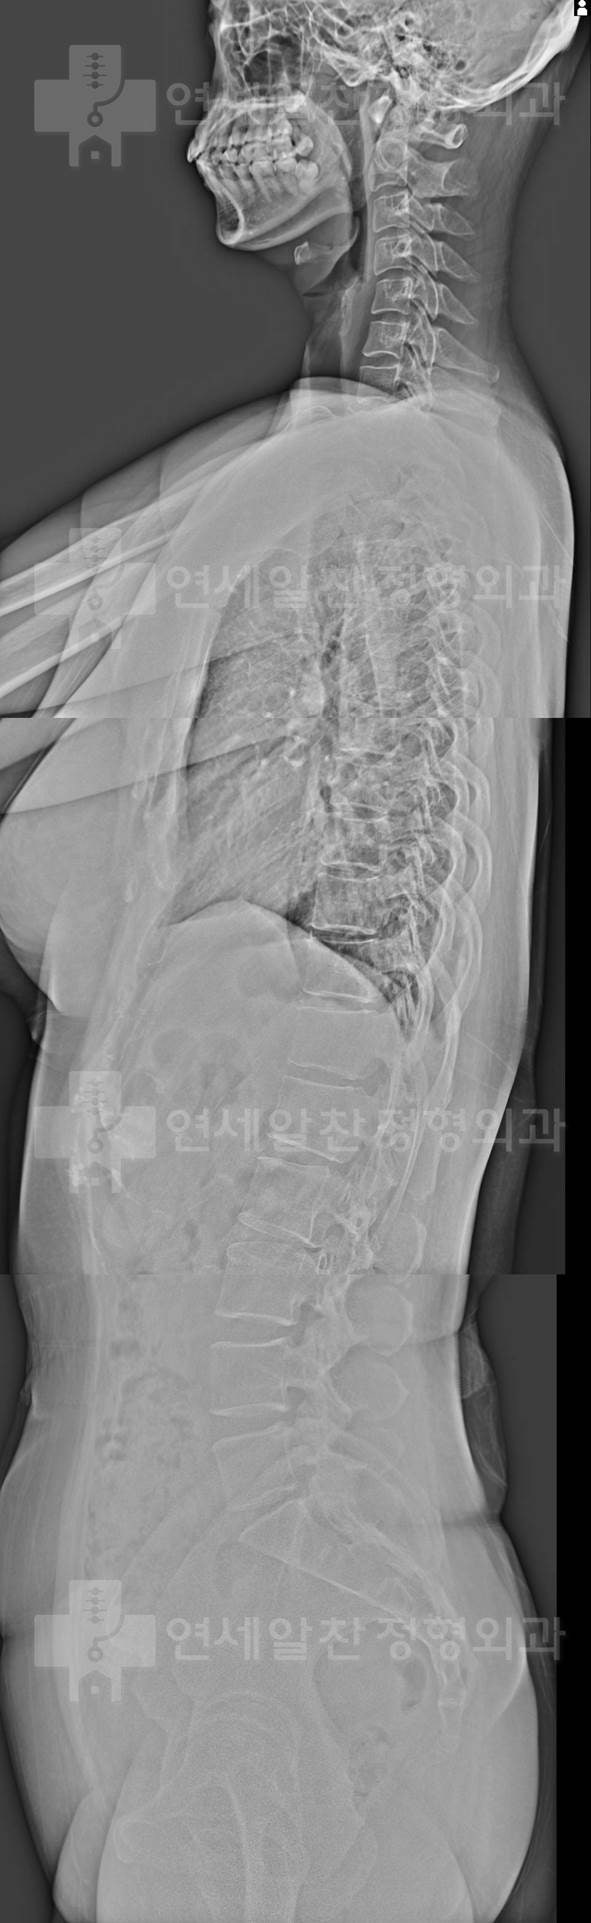

어깨의 가동범위 확보를 위해서는 물론 어깨 관절 자체의 문제만 해결해도 좋아지는 경우들이 많다. 하지만 흉추의 문제 또는 경추의 문제로 인한 기능부전이 동반되었을 경우 치료가 잘 되지 않는 경우들이 있다. 이 환자의 경우도 전체적인 사진에서 관찰해 보면

척추의 전만, 후만이 형성되지 않고 straight spine을 보인다. 특히 흉추의 후반이 소실되어 흉추의 가동성 확보가 되지 않아 견갑골의 안정성 및 움직임에 문제가 있을 가능성이 아주 많은 상태로 이에 대한 재활을 시행하였다. 외국에서 거주하는 사정으로 homework 위주로 진행하였으며 외국에서도 재활치료 병행을 권고하였다. 고맙게도 3개월 뒤 다시 본원을 내원하여 경과 관찰을 할 수 있었다. 환자는 통증 및 가동범위가 많이 개선되었다고 하였다.

아직 부족한 점이 많이 있으나 이전과 비교하여 가동범위 제한은 훨씬 개선된 상태이며 앞으로도 흉추 및 견관절의 재활을 꾸준히 권고하였고 한국에 며칠 있지 않았으나 본원의 센터에서 열심히 재활을 하고 배우고 다시 만날것을 기약하였다. 외국에서도 찾아오시는 분을 보면 조금더 정확히, 제대로 치료를 해야 겠다는 생각을 다시 한번 되새기게 된다.